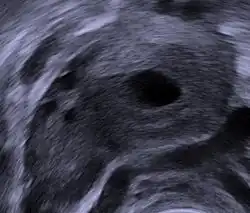

Vaginal ultrasound showing a corpus luteum in a pregnant woman, with a fluid-filled cavity in its center

If the egg is fertilised and implantation occurs, the syncytiotrophoblast (derived from trophoblast) cells of the blastocyst secrete the hormone human chorionic gonadotropin (hCG, or a similar hormone in other species) by day 9 post-fertilisation.

Human chorionic gonadotropin signals the corpus luteum to continue progesterone secretion, thereby maintaining the thick lining (endometrium) of the uterus and providing an area rich in blood vessels in which the zygote(s) can develop. From this point on, the corpus luteum is called the corpus luteum graviditatis.[17]